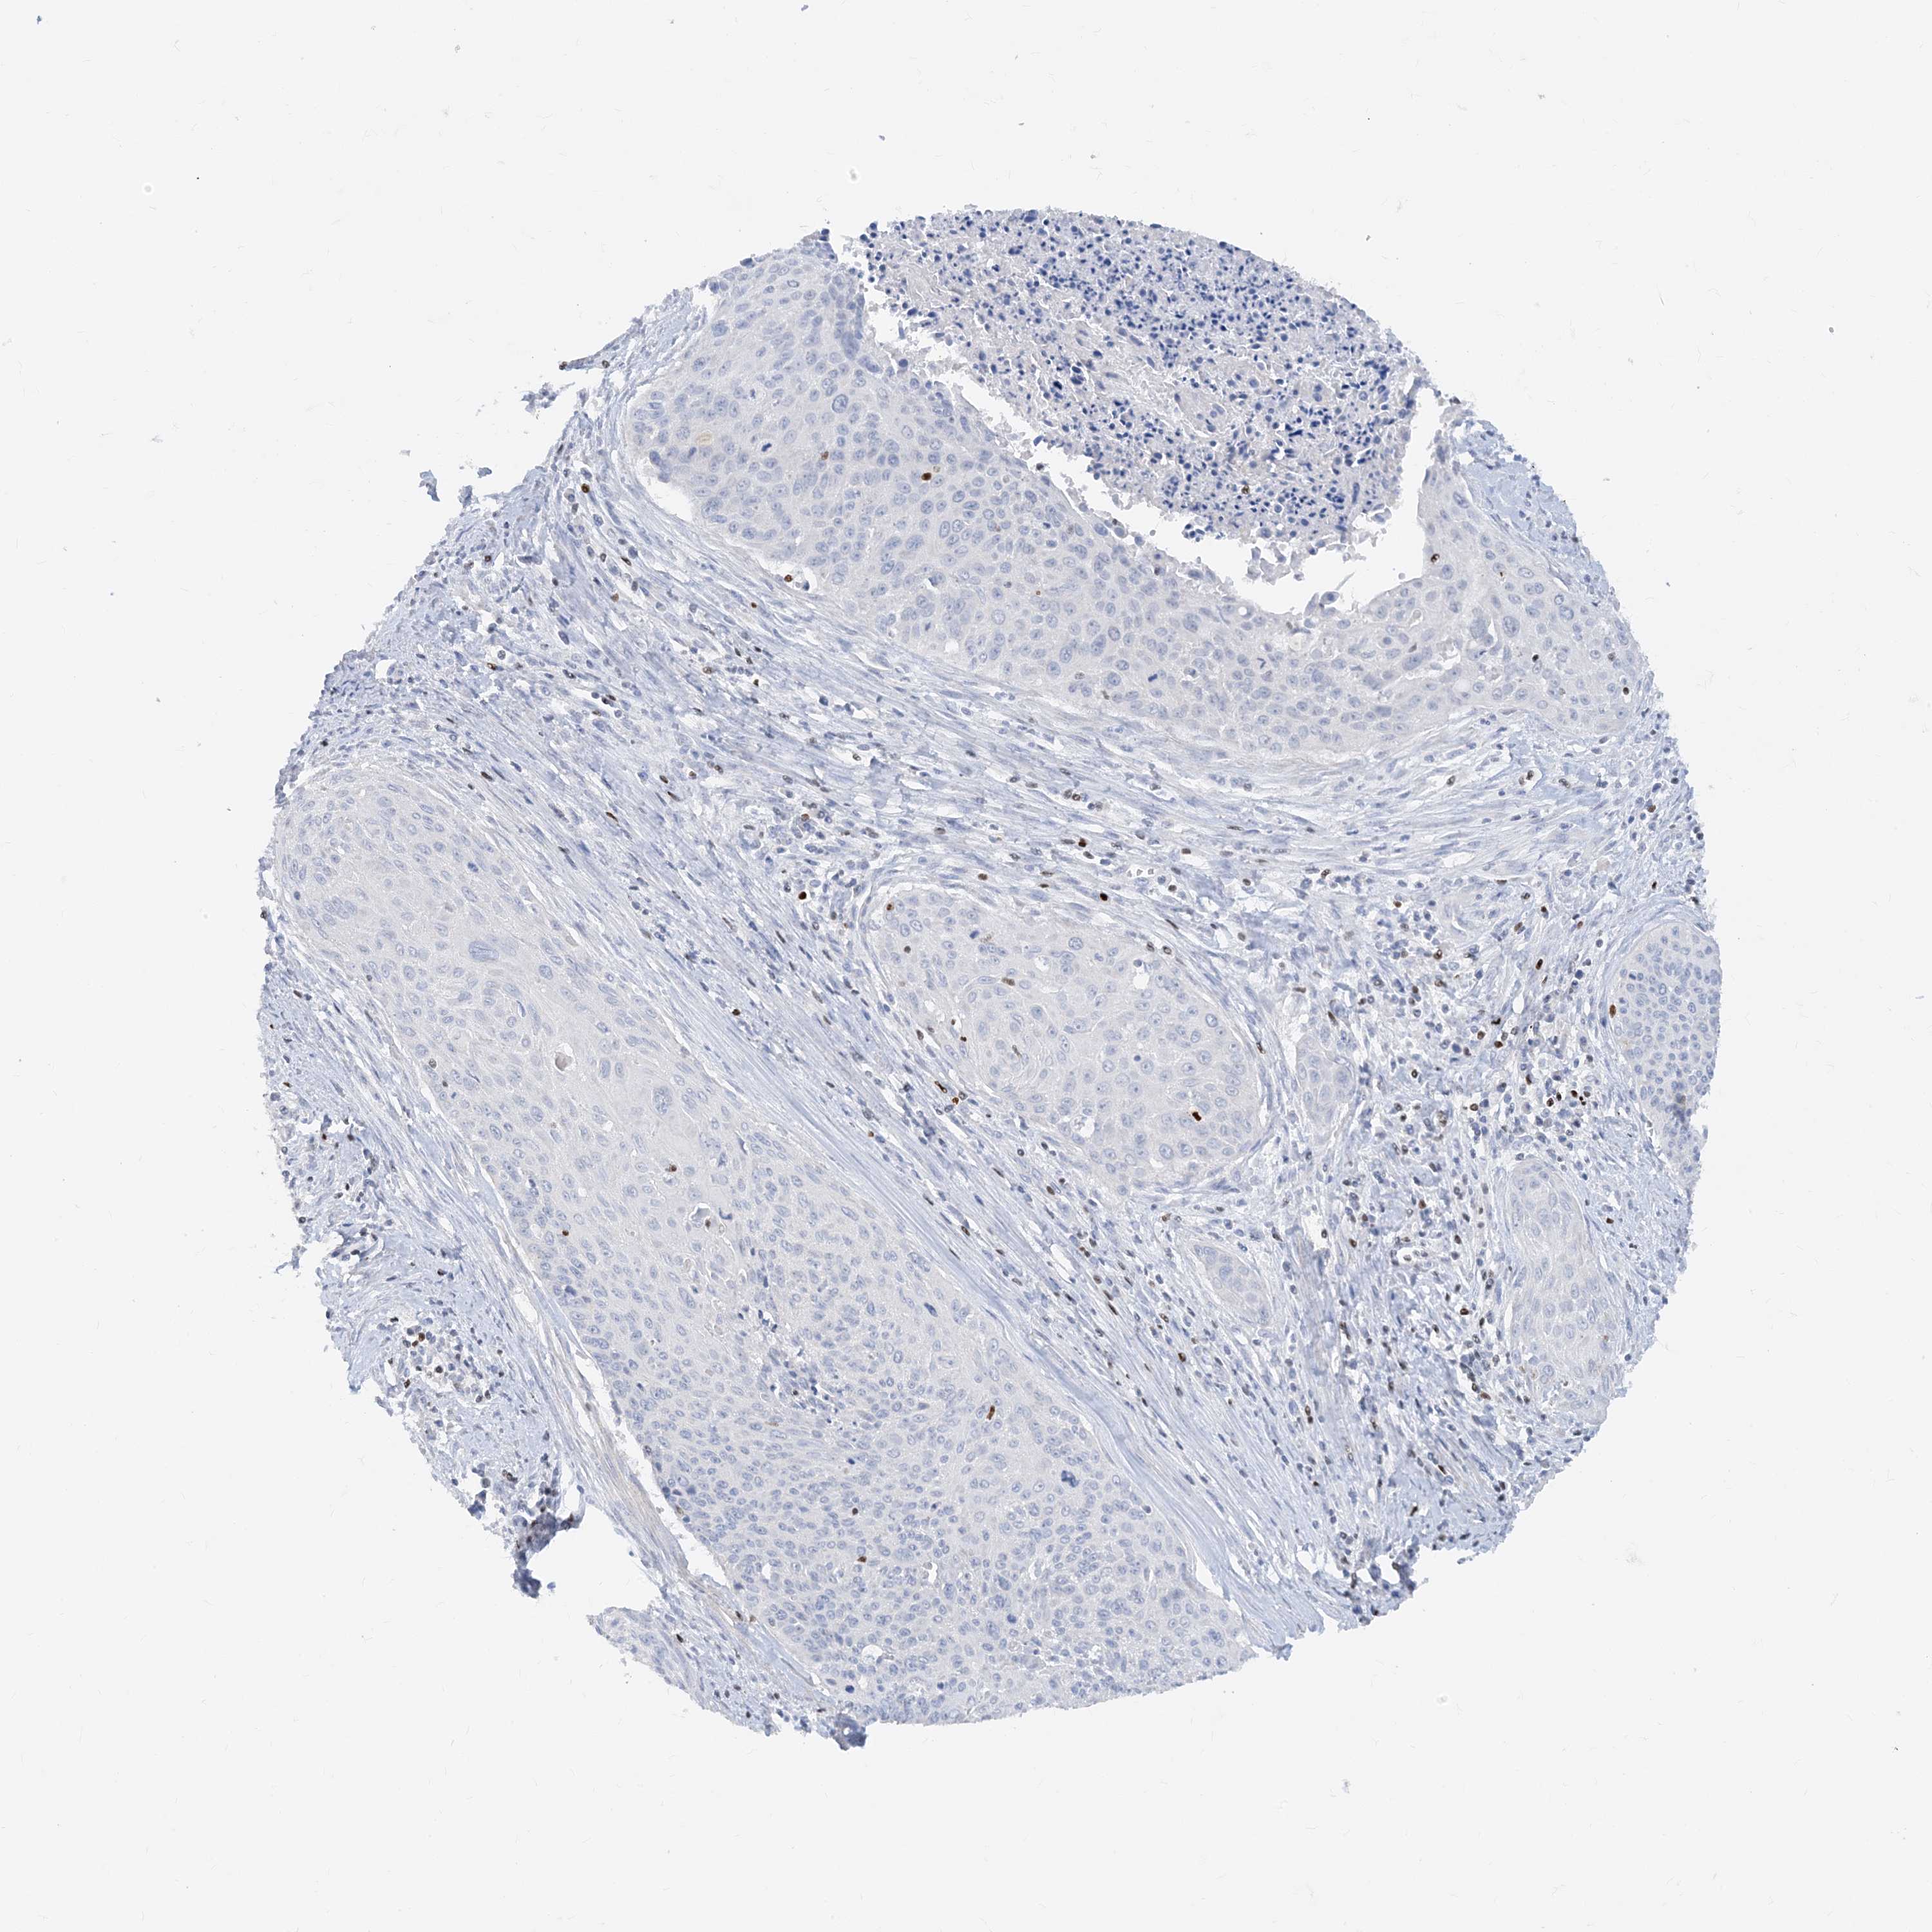

TBX21